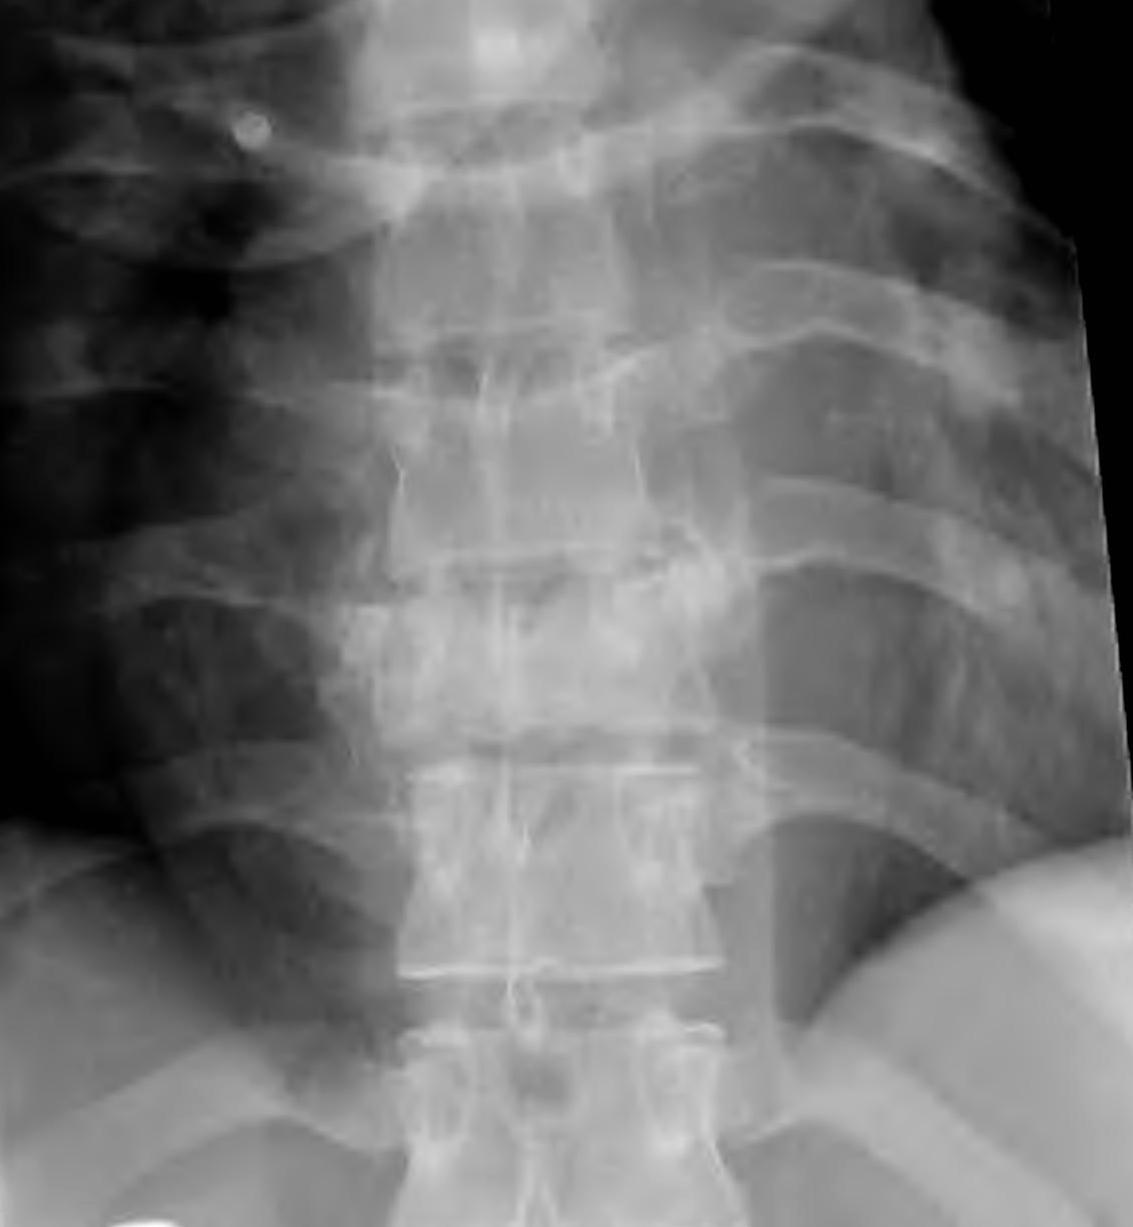

X-ray

- pedicle widening on AP

- widening of pedicles on AP

- decreased posterior body height compared to anterior